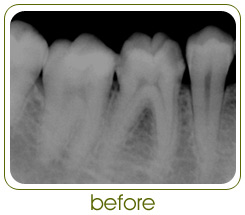

Root Canal Treatment is a procedure in which the nerve

canal of tooth is cleaned, disinfected and filled.

Contrary to popular belief, Root Canal Treatments have

come to be largely painless, predictable and

non-time-consuming procedures.

*All clinical pictures and x-rays on this website are those of cases done at

Doctors Dental Clinic only.